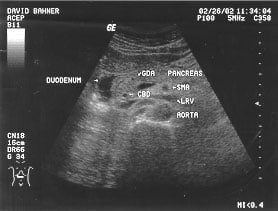

Aorta - renal (labeled)